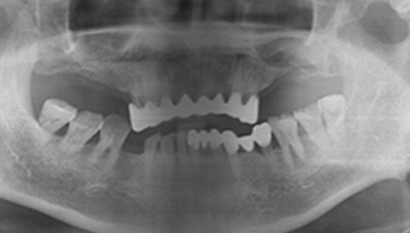

W Dental Clinic Before & After

治療前後の写真

Before

After